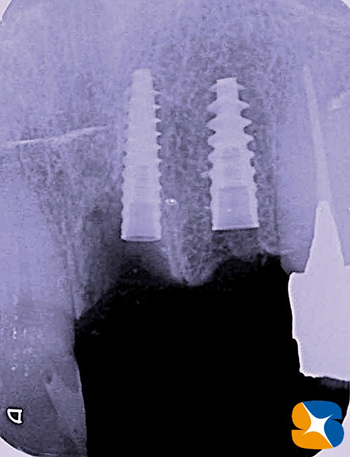

左下のレントゲン。

右上のレントゲン。